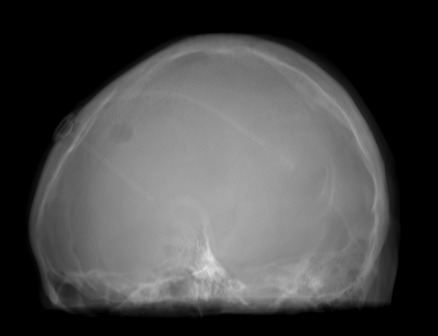

(f) Guide 𝑮𝑮\boldsymbol{G}

Refer to caption

(g) Input 𝑰𝑰\boldsymbol{I}

(h) Guidance map 𝑴𝑴\boldsymbol{M}

(i) Prediction 𝑷𝑷\boldsymbol{P}

(j) Ground truth

Figure 2: Inputs and outputs of the guided filtering pipeline based on the WDSR network. T1 & T2 MRI pairs (a)-(e) and CT & MRI projection images (f)-(j).

In Fig. 2 and 4, exemplary input, output and label images of the pipeline are presented for both tasks. Additional super-resolved images for both network architectures with and without the guided filter can be seen in Fig. 3. The results show a consistently high quality over both, the tomographic and the projective domain, as well as both tasks. Corresponding quantitative evaluation can be found in Table I and II. For SR, the WDSR network, i.e., the designated super resolution network, performs consistently better for both datasets with and without the guided filter. Applied to the tomographic images, the approaches without the guided filter deliver slightly better quantitative results. For the projection images this difference diminishes and both approaches are on par. In the case of denoising, the approaches with the guided filter deliver a lower mean absolute error while the structural similarity is increased without it. Though, the measurable differences are only marginal. The results generated by the plain guided filter without the learned guidance map are numerically worse than the approaches empowered by the guidance map generator for all tasks. This observation is most prevalent when observing the results of the tomographic T1 and T2 Flair images for SR, while for denoising the results are closer to the deep learning-based approaches.

In general, the decrease in image quality metrics w.r.t. to smaller radii is much stronger for the tomographic T1 and T2 Flair images than for the projection images. We assume the reason for this to be the difference in resolution of both datasets. The projection images resemble the ground truth more closely from the outset when compared to the tomographic images as seen in Fig. 2(b) and 2(g), respectively. Consequently, more information has to be generated by the networks. As the guided filter is sensitive towards correlation between the input and guidance map the constraints on the applicable changes are more severe.